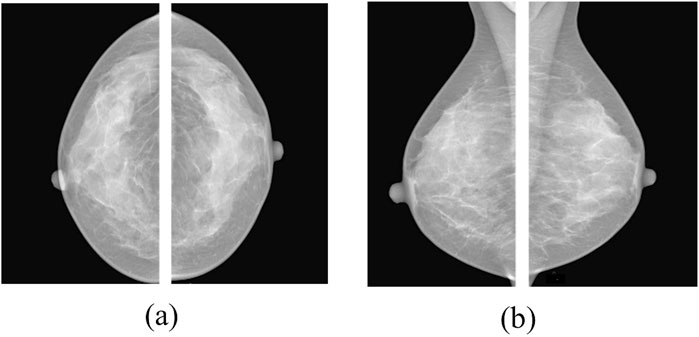

The INbreast dataset is a high-quality, full-field digital mammography (FFDM) resource that plays a pivotal role in the development and evaluation of computer-aided diagnosis (CAD) systems for breast cancer. Collected at the Centro Hospitalar de S. João in Porto, Portugal, the dataset comprises 410 mammographic images from 115 cases, captured using a Siemens Mammomat Inspiration system with 70μm pixel pitch and 14-bit depth (Moreira et al., 2012). What sets INbreast apart is its meticulous, expert-driven annotation protocol. Each case includes precise radiologist-delineated contours for various lesion types, including masses, calcifications, asymmetries, and architectural distortions, ensuring reliable ground truth for both detection and classification tasks. Annotations are provided in structured XML format, facilitating straightforward integration into machine learning pipelines. Beyond its technical precision, INbreast captures a broad spectrum of mammographic presentations, from normal cases to diverse pathological abnormalities. This diversity makes it particularly suitable for developing and benchmarking deep learning models aimed at early and accurate diagnosis. Figure 8 shows representative samples from the INbreast dataset.

Figure 8

Two mammogram images labeled (a) and (b). Image (a) shows dense breast tissue with less distinct features, while image (b) displays more defined tissue patterns with varying density.

Figure 8. Typical images from the INbreast dataset: (a) Craniocaudal (CC) and (b) mediolateral oblique (MLO) views of both breasts (Ahmed and Nandi, 2024).